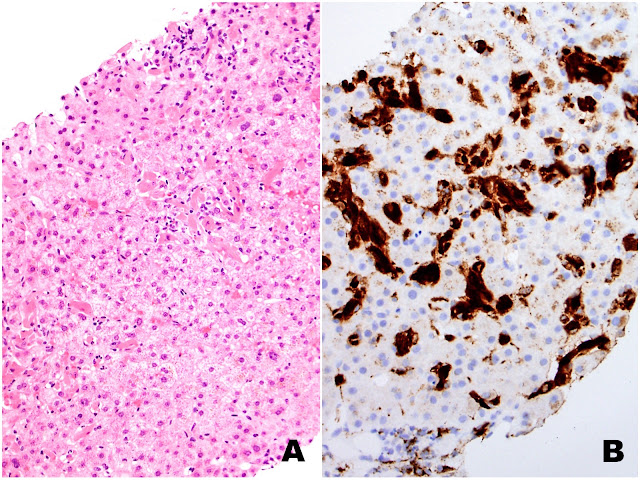

| Figures 1A (H&E) and 1B (CD68) |

The liver biopsy shows extensive sinusoidal infiltration by bland appearing plump eosinophilic cells with somewhat retractile or granular cytoplasm (Figures 1A and 2A). These cells are positive for CD68 confirming they are histiocytes (Figures 1B and 2B). The histiocytes contain crystalline immunoglobulin kappa highlighted on the Ig kappa and PAS-D stains (Figures 3A and 3B, respectively). Ig lambda was negative.